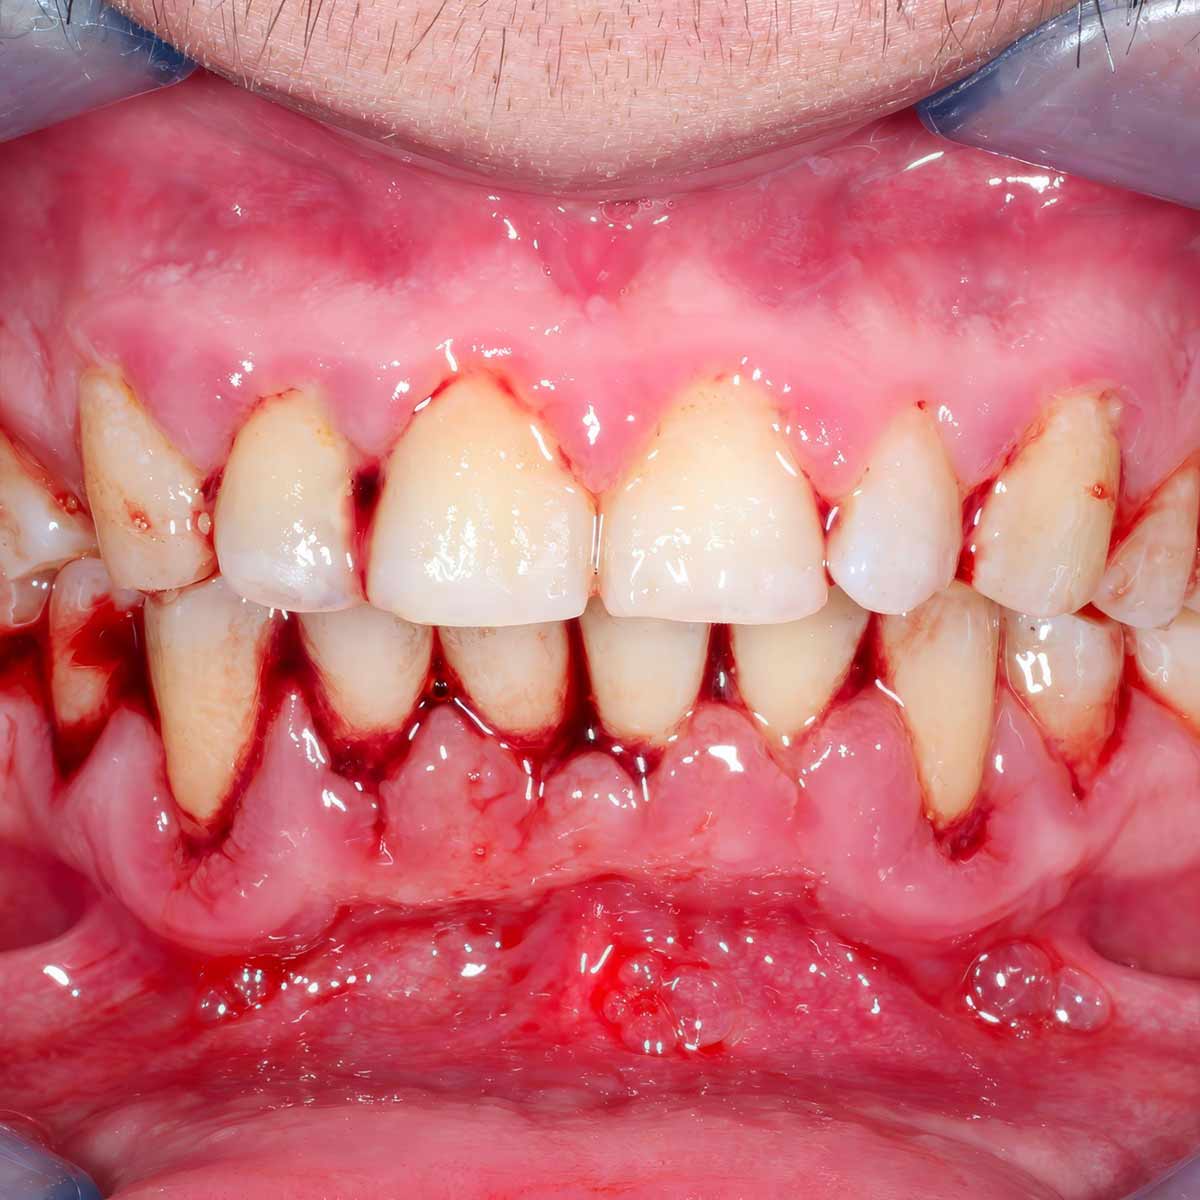

Síntomas de la gingivitis

Los síntomas comunes de la gingivitis incluyen:

- Encías rojas, inflamadas y sensibles

- Sangrado de encías al cepillarse o usar hilo dental

- Mal aliento persistente

- Encías que se separan de los dientes

Si experimentas alguno de estos síntomas, es importante actuar rápidamente para evitar que la gingivitis avance a periodontitis, una forma más grave de enfermedad de las encías.